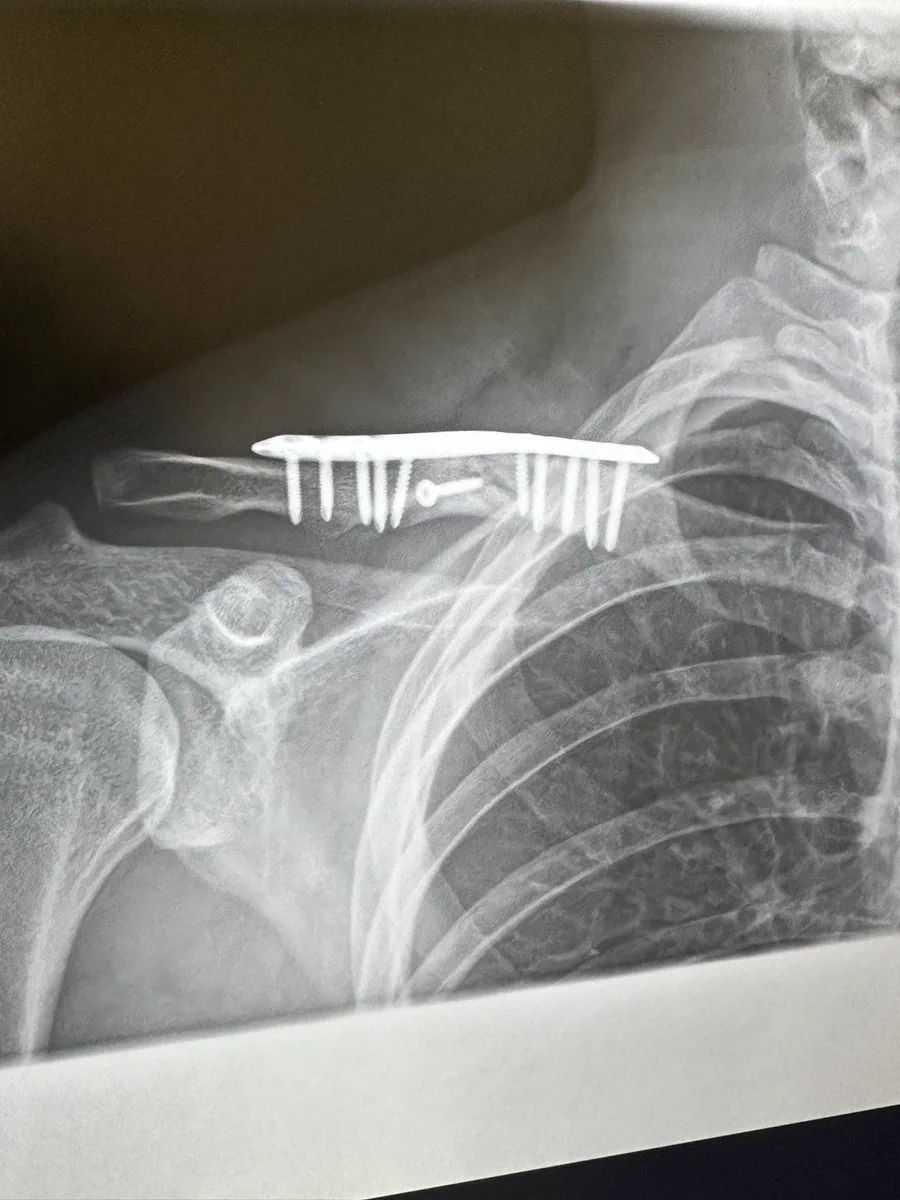

鎖骨を骨折?!レントゲンで見たら折りたためるクシみたい!

鎖骨を骨折されているツイート主さん。治療中なのでしょうか。レントゲンの画像を見ると、鎖骨の部分に痛そうな物体がはっきりと写っています。まるで折りたたんで持ち歩きができる櫛みたいですね。そういわれるとそうとしか見えませんが、お大事にしていただきたいです。

鎖骨の治療中にレントゲンを撮影したら、折りたたみの櫛のようなものが写った!という画像のツイートでした。

鎖骨の骨折治療はこのようになるのだということを初めて知りましたが、リプ欄では同じ経験をされたとおっしゃっている方も多かったです。櫛の真ん中の部分にはっきりとネジが写っていて、これもまた、折りたたみのクシに見えてしまいますよね。